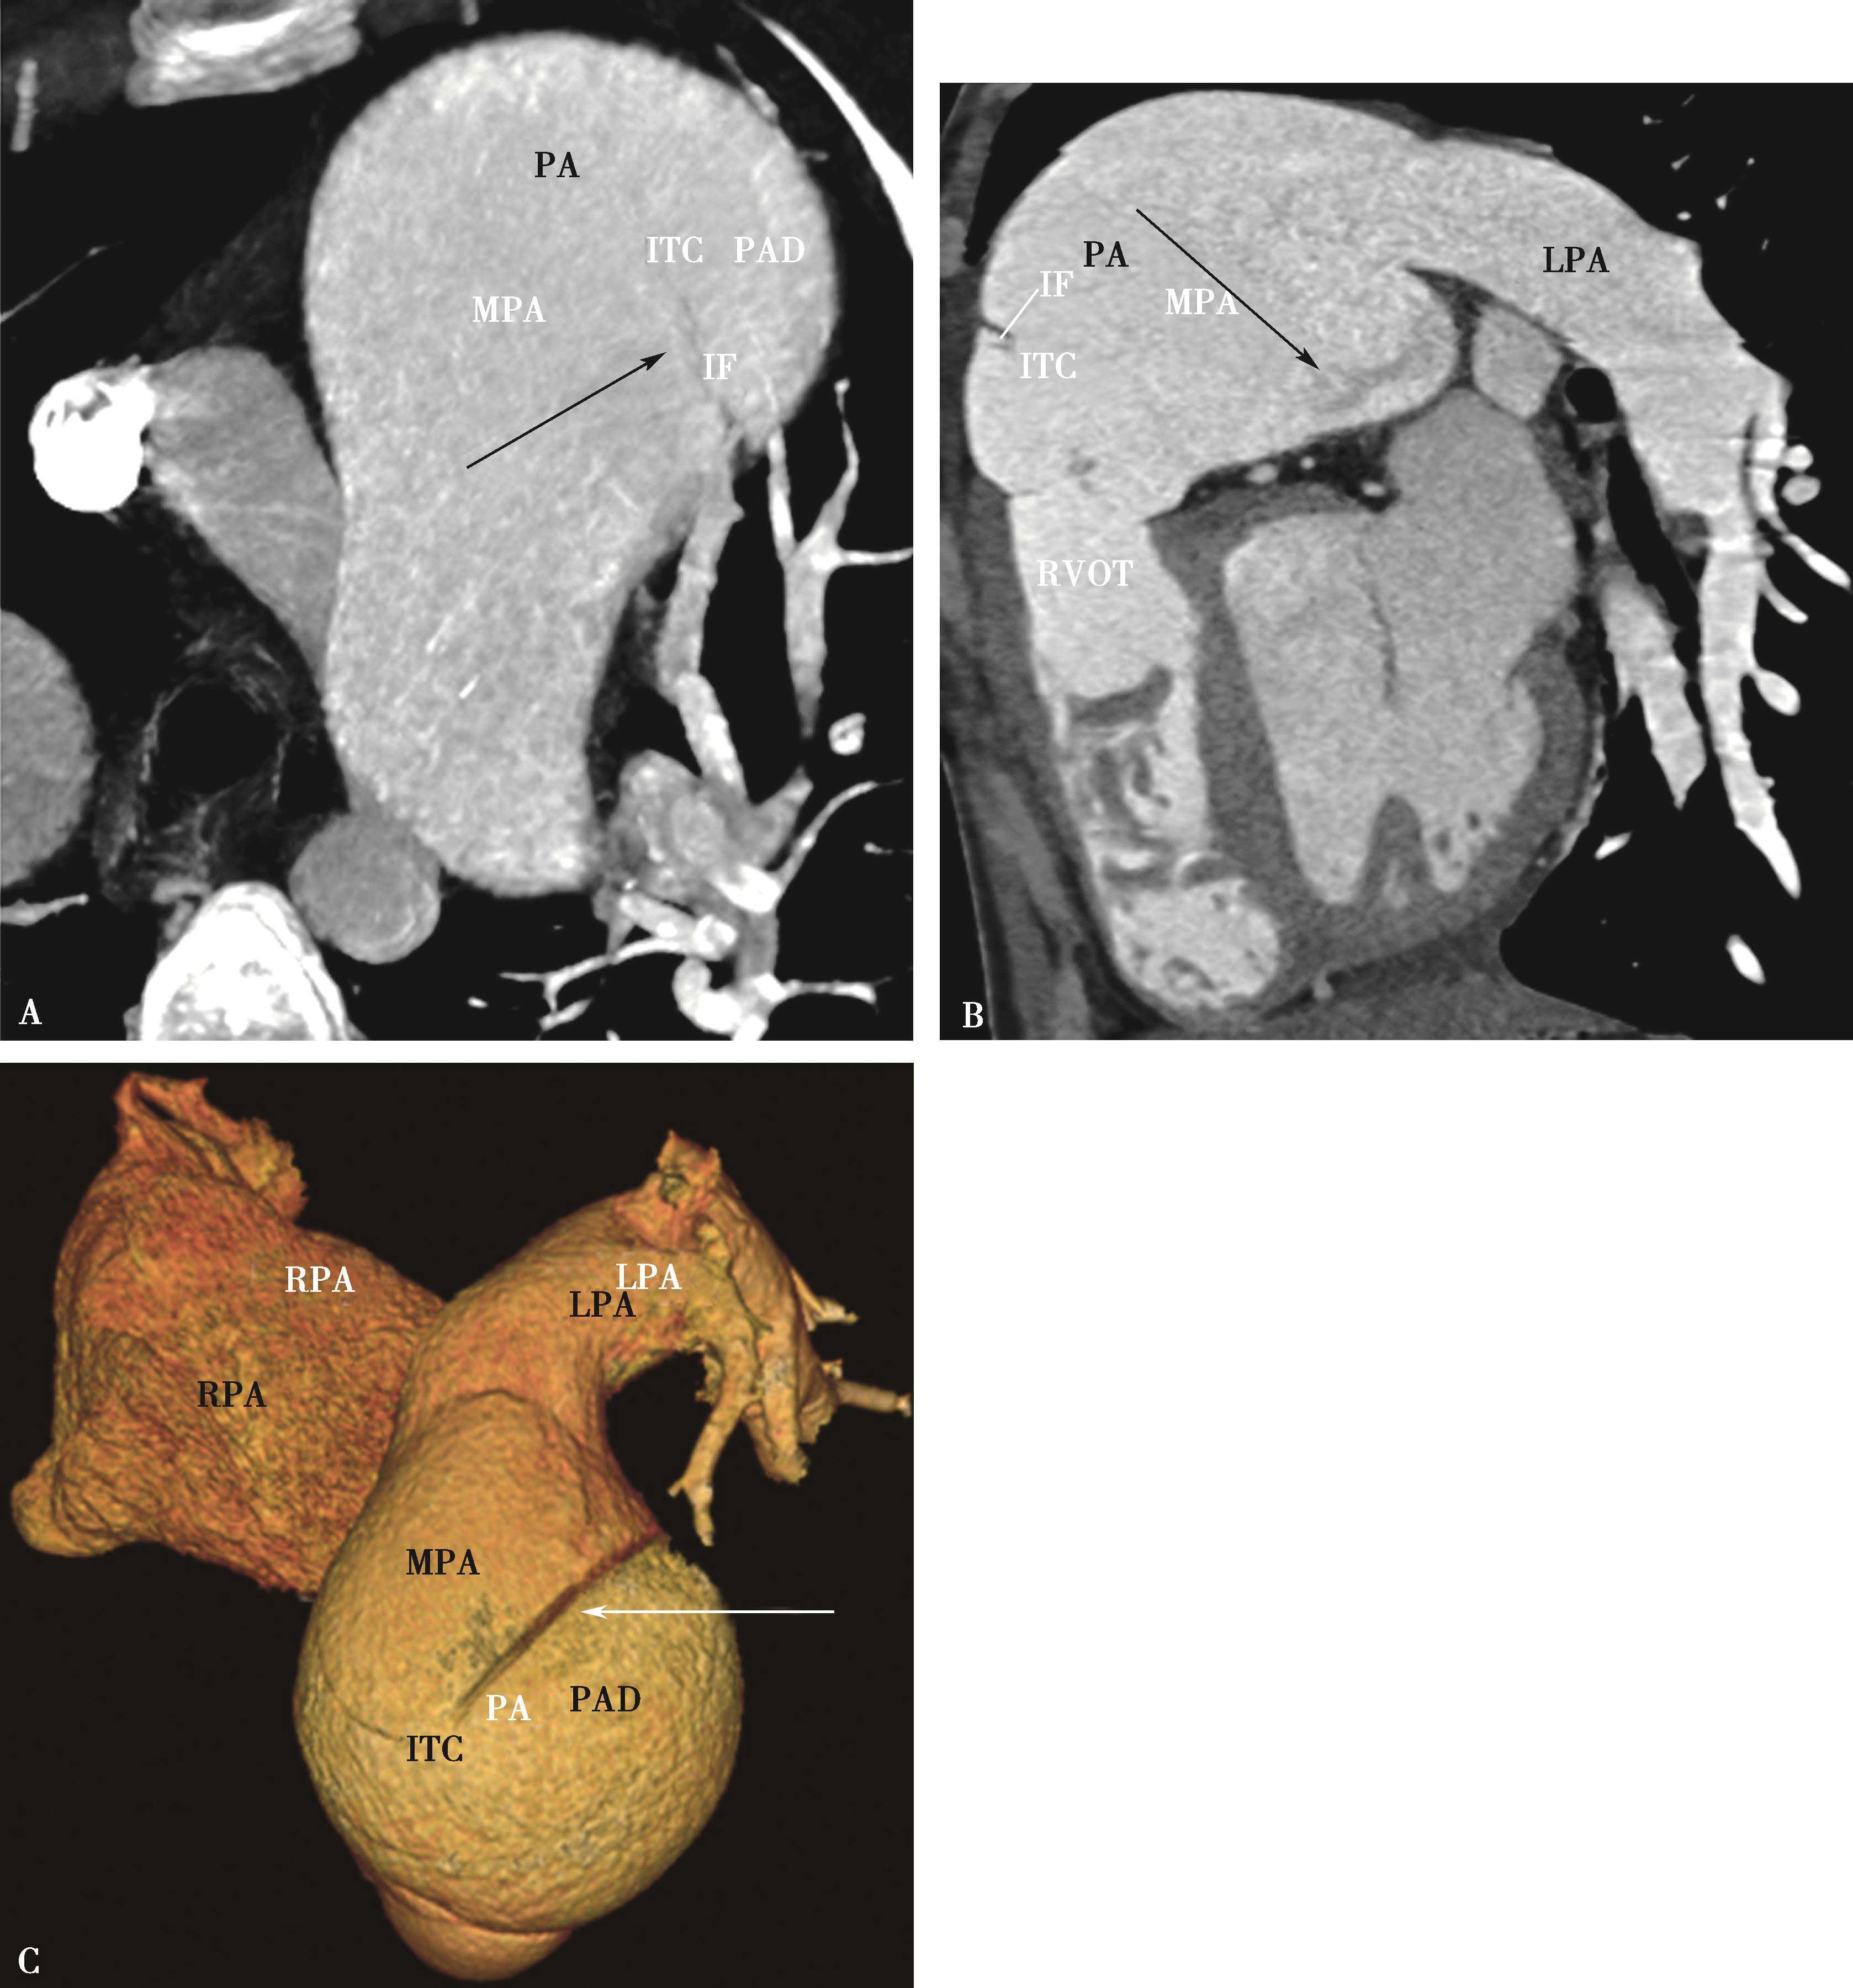

图8-7-2 男,44岁,因劳力性胸闷、气短2年余,加重1个月并出现双下肢水肿急诊入院

CT横断扫描ABCD示主肺动脉、右肺动脉干内巨大充盈缺损,膨胀性生长,累及右心室流出道(↑),主肺动脉明显扩张。肺动脉造影E,示主肺、左右肺动脉干及右下肺动脉管腔内充盈缺损(↑),两肺、左肺舌叶及下叶各基底支仅见稀疏肺动脉分支显影。病理诊断为恶性间叶细胞瘤。